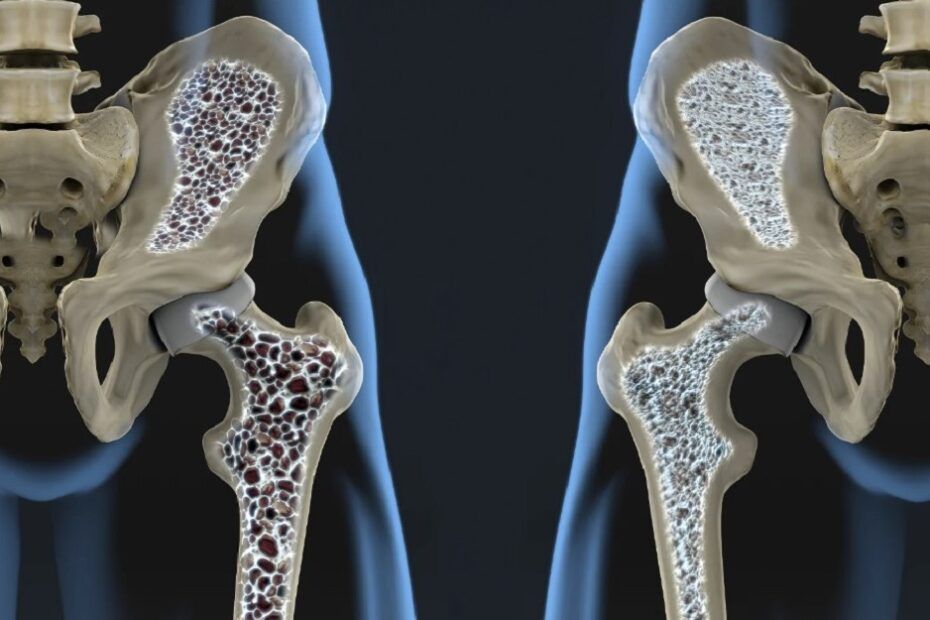

Osteoporoza este o afecțiune în care oasele devin extrem de fragile și subțiri. Persoanele cu osteoporoză prezintă un risc mai mare de fracturi osoase bruște și neașteptate, în special la nivelul șoldului, încheieturii mâinii și coloanei vertebrale.

Corpul uman se descompune în mod constant și înlocuiește țesuturile osoase. Cu toate acestea, odată cu îmbătrânirea (sau din cauza modificărilor hormonale sau a lipsei de calciu și Vitamina D), rata de creare de noi țesuturi osoase încetinește și rata de descompunere a osului devine mai rapidă.